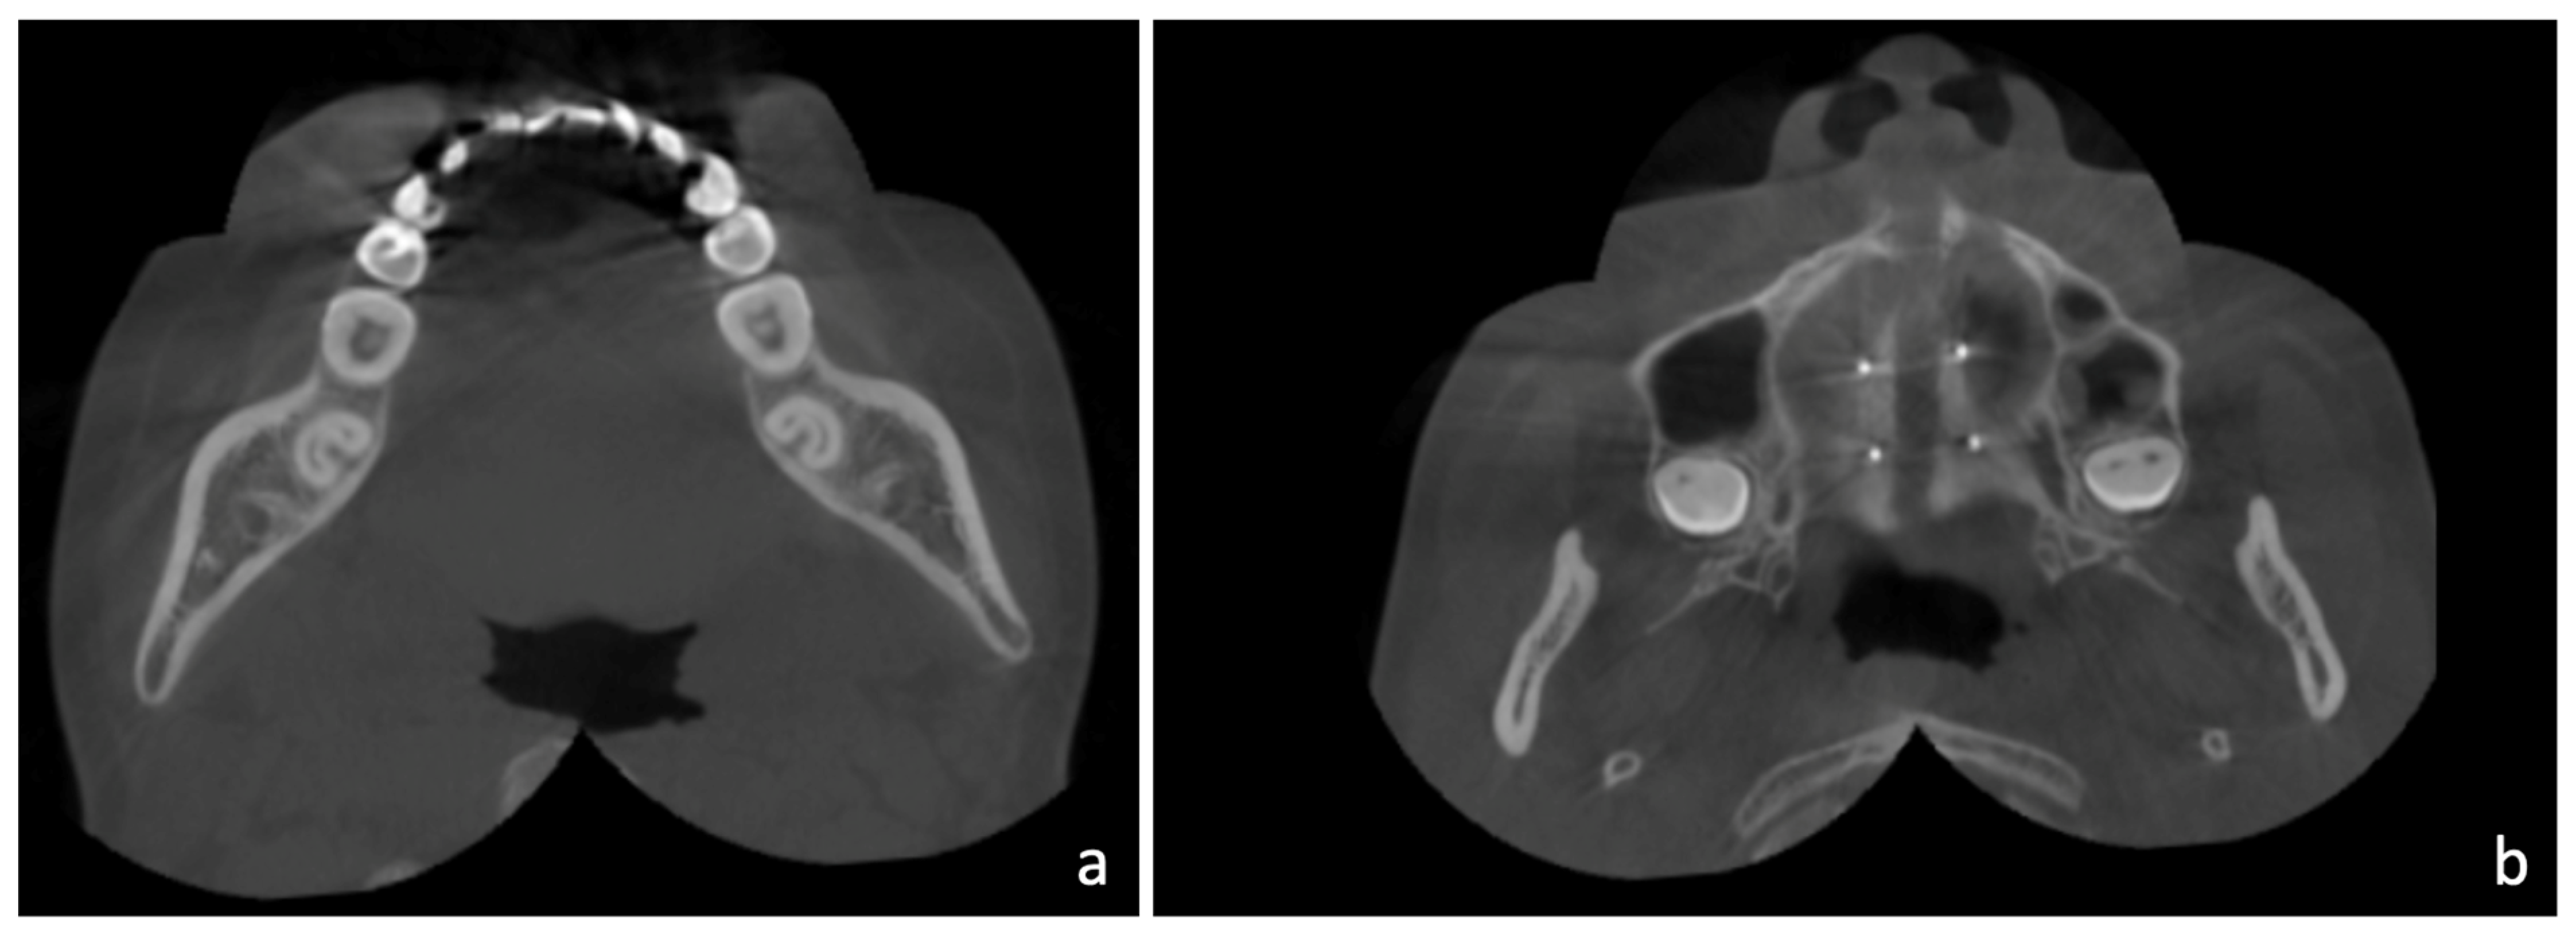

2. Case Report

2.1. Diagnosis and Aetiology